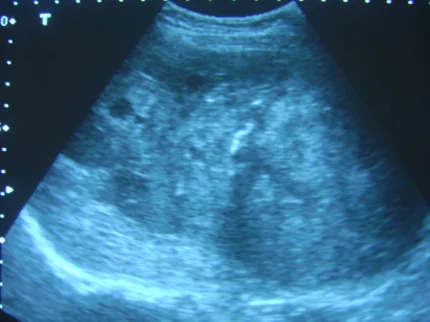

這題的解題核心在於仔細判讀兩張肝臟超音波影像的內容,並結合醫學知識判斷哪個敘述是錯誤的。圖片中清晰可見肝內腫塊、膽結石以及肝門靜脈結構。